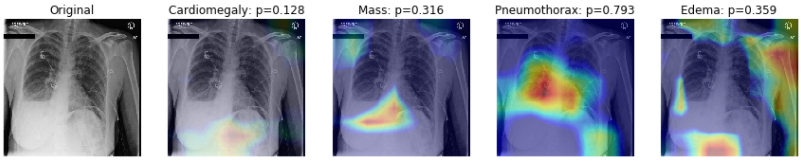

5.2 Visualizing Learning with GradCAM

: GradCAM 기술을 사용하여 병리학적 상태를 예측하기 위해, 이미지의 중요한 영역을 강조하는 히트맵을 생성

: 먼저 작은 Training 셋을 로드하고, 앞서 AUC 측정값이 가장 높은 4개의 클래스를 살펴볼 것

: 몇 가지 특정 이미지들을 확인

util.compute_gradcam(model, '00011355_002.png', IMAGE_DIR, df, labels, labels_to_show)

: P 값은 정답 클래스의 softmax probability를 의미함